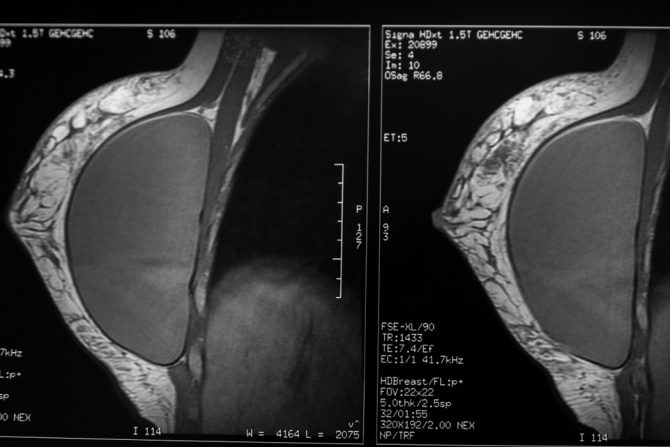

Implantati u dojkama povezani su sa određenim karcinomima koji mogu da se razviju u ožiljnom tkivu koje se formira oko implantata, upozorava američka Uprava za hranu i lekove FDA. Tim povodom FDA je izdala upozorenje napominjući da se ovi karcinomi razlikuju od anaplastičnog limfoma velikih ćelija povezanih sa implantatima dojke (BIA-ALCL), oblika raka koji ima veze sa implantatima u grudima na koji je agencija ranije upozoravala.

Karcinomi, koje je FDA označila - karcinom skvamoznih ćelija (SCC) i različite karcinome imunog sistema (limfome), povezani su sa svim vrstama implantata, bilo da su glatki ili teksturisani, ili punjeni fiziološkim rastvorom ili silikonom. Rak se formira u ožiljnom tkivu oko implantata, koje je u struci poznato kao kapsula.

Novoobjavljeni karcinomi jesu retki, a FDA navodi da je preliminarni pregled naučne literature pokazao pojavu manje od 20 slučajeva karcinoma skvamoznih ćelija i manje od 30 slučajeva limfoma, u kapsuli oko implantata dojke. Zbog toga će nastaviti da prikuplja i pregleda sve dostupne podatke o karcinomima u kapsuli oko implantata u grudima.